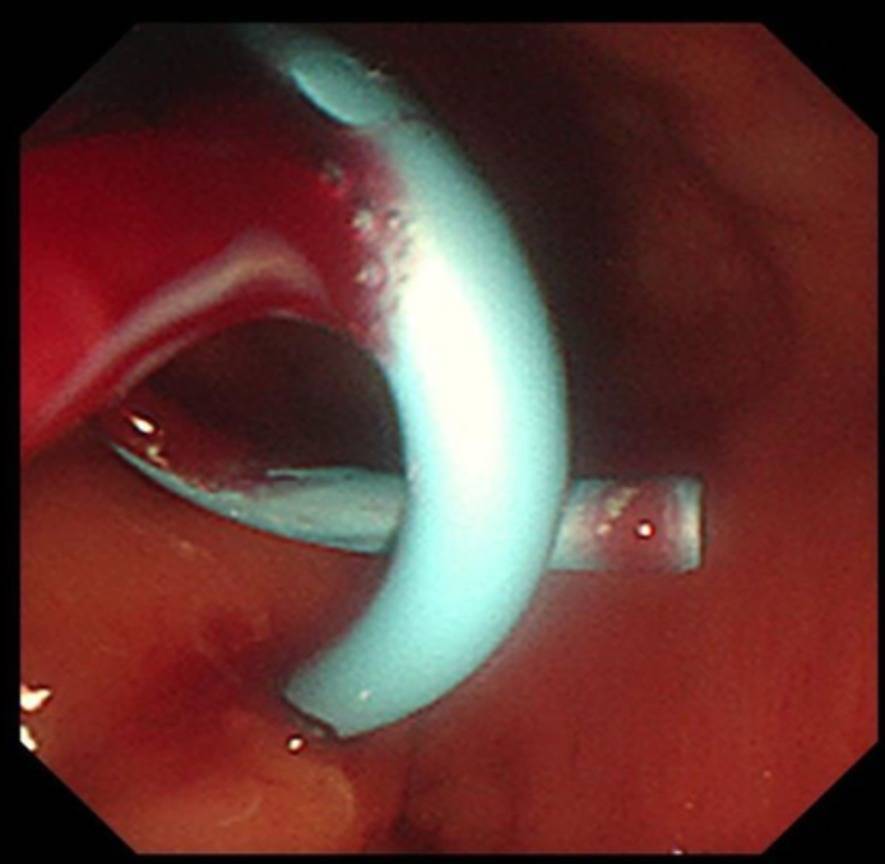

置入后的直肠内支架

经过充分的术前准备,消化内科刘华副主任医师在毛涛主任的指导下,和麻醉科、内镜室医护团队的密切配合下,凭借精湛的内镜技术,仅用时20分钟,便通过实时超声精准锁定病灶位置,巧妙避开血管、神经等重要解剖结构,合理规划穿刺路径并成功置入支架。手术全程经人体自然腔道操作,无体表切口,且未对直肠功能造成损伤。